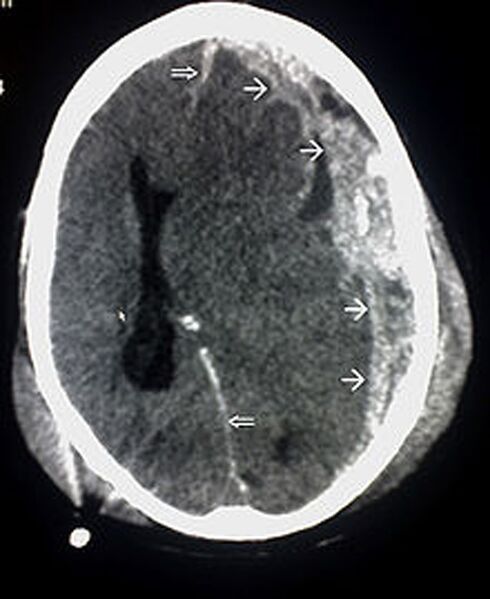

Beschreibung Röntgenaufnahme einer Gehirnerschütterung

Originaltitel Dieser CT-Scan ist ein Beispiel für ein subdurales Hämatom durch Trauma; Einzel Pfeile markieren die Ausdehnung des subduralen Hämatoms; Doppel Pfeile markieren die Mittellinenverlagerung